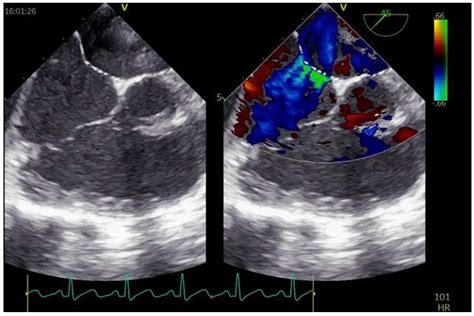

640×640

researchgate.net

TEE-guided PFO device closure. A 40-year-old woma…